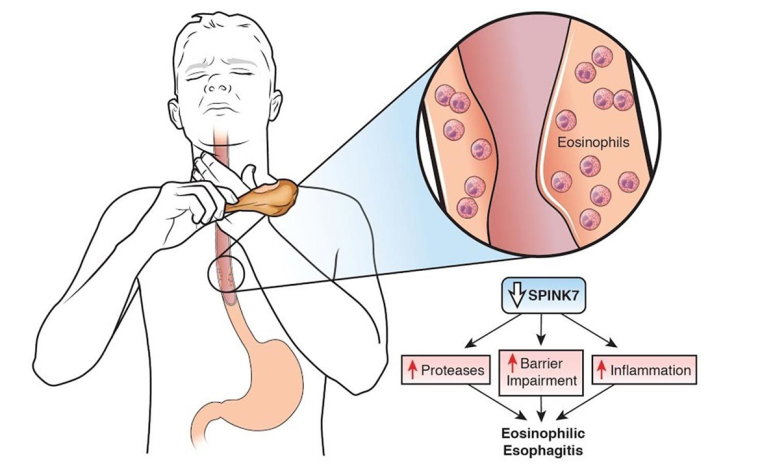

메커니즘 호산구 식도염의 발생 메커니즘을 알아보겠습니다IgE와 관련된 음식알레르기, 알레르기 비염, 천식, 습진과 같은 알레르기 관련 질환이 호산구 식도염 환자에게 자주 보고되고 있습니다.

현재 명확하게 제시된 메커니즘은 없지만 nature에 발표된 리뷰에 따르면 산 노출로 식도의 epithelial barier injury가 발생하면 해당 부위에 음식, aeroallergen이 epithelial barrier를 가로질러 식도 내로 들어가게 됩니다. 이렇게 들어간 외부 allergen은 면역세포(Th2 cell, Mast cell, 호산구 등)에 의해 염증반응이 증가합니다.

이 염증반응에 의해 혈관의 신생합성이 증가하여 근육층이 두꺼워지고 섬유화가 진행되어 식도의 운동성을 저하시키고 내강이 좁아지는 담보이기 때문에 음식통과를 위한 경로가 적어집니다.